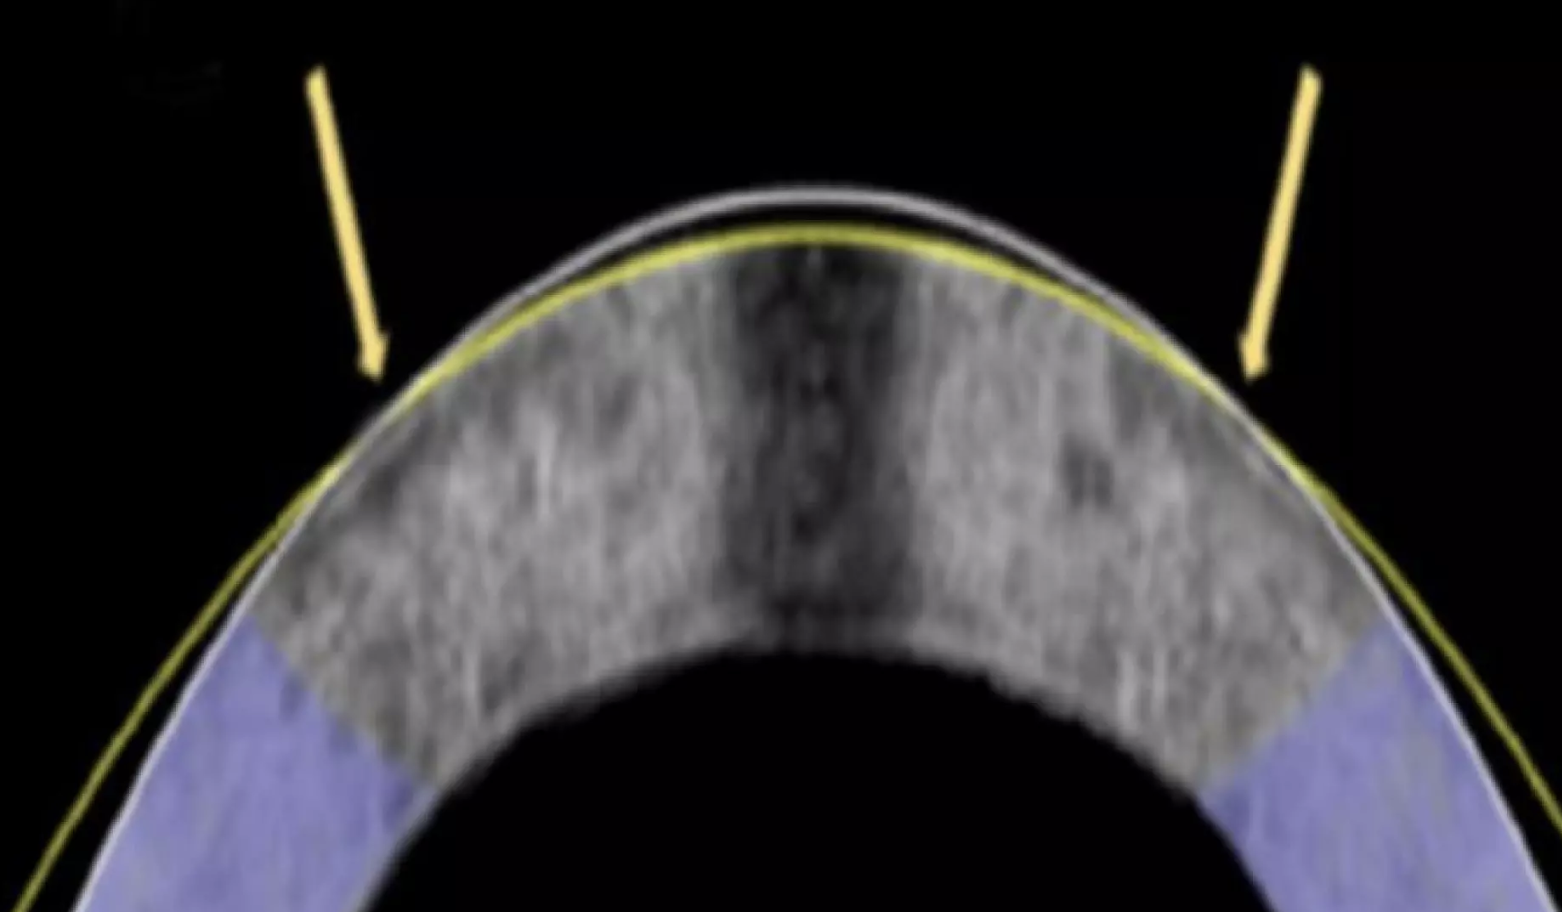

image.png

Короче пишу если кому интересно.

Делал ReLEx Smile в 2023м. Зрение улучшилось с -8 и -7.5 до -0.75 и -0.5 через месяц после операции. С тех пор пока не менялось.

Сама операция довольно неприятная. В брошюрах пишут что ничего не почувствуешь, я лично почувствовал и быть морально готовым не помешало бы, потому что потом после операции долго нервничал что может я чет закосячил, так как там нельзя во время работы лазера было шевелить глазом, а я шевелил.

Сама операция без боли, да, но неприятные ощущения проникновения в глазик во время - определённо были.

Плюс: везде пишут что после Смайла можно чуть ли не сразу возвращаться к привычному образу жизни, идти на работу, заниматься спортом, только без сауны и бассейна какое-то время, пока заживает роговица.

Я бы советовал всё равно взять полноценный отпуск на месяц или даже больше, особенно если зрение изначально было не очень, как у меня. Я сам после операции отдыхал неделю и мне этого оказалось недостаточно. Быстро возвращаться к постоянным зрительным нагрузкам оказалось довольно ощутимо. К тому же там ещё по постоперационным показаниям нужно месяц везде ходить в тёмных очках, да ты и сам их не снимешь, потому что будешь охуевать от солнечного света.

Сухость, эффект от фар машин ночью типа пикрил - были и есть, хоть и не такие ярко выраженные, как некоторые пишут. Симптомы ослабели спустя где-то полгода, но полностью так до сих пор и не прошли, регулярно капаю увлажняющие капли, слежу за тем что бы пить достаточно воды, и стараюсь делать перерывы, но всё равно сухость остаётся.

С ней как бы можно жить, но тем не менее до операции я вообще не знал что такое сухость глаз.

Эффект ночных фар не мешает, тоже спустя какое-то время после операции почти прошёл.

Вдобавок долго привыкал к тому что зрение на разных глазах отличается. Раньше линзы на очках корректировали разницу, а потом даже разница в 0.25 ощущалась сильно. Мозг привык только спустя полгода и то периодически осознаю что картинка не мгновенно становится чёткой при смене фокуса с одного предмета на другой. Уж не знаю следствие это операции или разницы в глазах. В общем нужно быть готовым к такой хуйне, что после операции зрение на глазах может быть разным и придётся привыкать.

В целом что могу сказать - если зрение хуёвое, от минус 5 до минус 8 и выше - делать однозначно стоит, посоветовавшись, понятно, с врачом. Потому что, насколько слышал, при таком минусе могут лазерную коррекцию и не одобрить, либо одобрить другую - одну из разновидностей фрк или лэсика, в зависимости от показаний, возраста и наличия других болячек и особенностей образа жизни военным и скалолазам вроде фрк делают всегда. Точно не уверен

Если зрение относительно нормальное и уже привык к очкам/линзам и вообще в принципе норм, то, мне кажется, лучше ситуацию не менять.

Я лично вообще не пожалел. До операции регулярно побаливали глаза и голова, вплоть до мигреней из-за хронического перенапряжения. Теперь голова болит намного реже. Хотя бы ради этого оно того стоило. Ну и хорошее зрение конечно круто. После операции прикольно было просто ходить и наслаждаться графоном, детализацией. Сейчас привык и похуй.